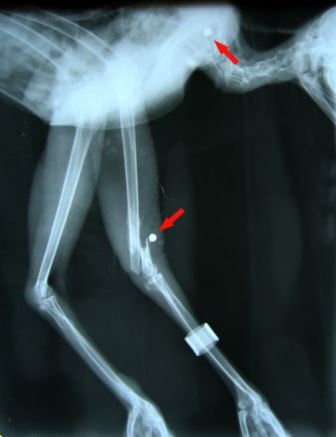

Deze week werd in het Natuurhulpcentrum een lama opgevangen. Deze grote familieleden van de kameel worden soms als huisdier gehouden, maar de eigenaars van “onze” lama konden er niet meer voor zorgen en zochten een nieuwe thuis voor hun huisdier.Met behulp van twe

Natuurhulpcentrum